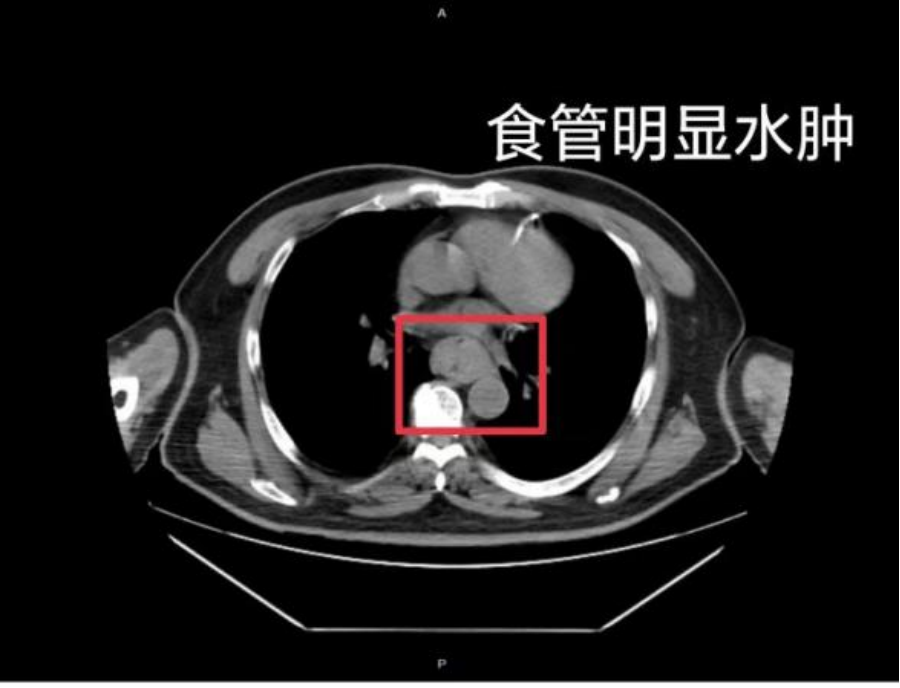

最近,福州有个人在网上说,他喝了一碗温度很高的福鼎肉片,结果吐血了,还检查出食道发炎肿大。这样的真实事例表明,吃得太烫的东西造成的损害并不罕见,大人小孩都有可能遇到这种情况。

医生说明,吃得太烫的东西会伤到口腔、食道和胃的内部皮层,造成皮层破损、发炎,甚至破溃流血流脓。老是这样刺激,会让皮层一直受损,提高得了食道发炎、肠胃破溃和转变成癌症的可能。轻微的食道被烫到或许没感觉,重一点的会感觉有东西堵着,咽东西也费劲。